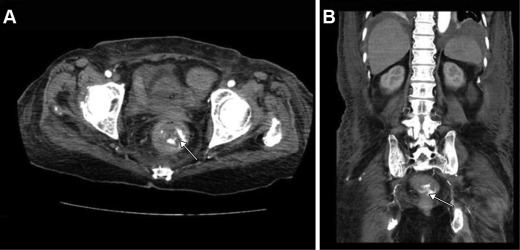

Three days later, computed tomography angiography (CTA) was performed after the patient had another episode of massive gastrointestinal bleeding. Contrast extravasation from the rectal wall was identified on CTA scans (Fig. 1 ). In addition, a small amount of ascites was demonstrated within the subphrenic space, which suggested possible congestive heart failure and hypoalbuminemia. After discussing the possible treatment options with a radiologist, we chose to repeat endoscopic examination first. A bilateral iliac angiography with subsequent embolization for rectal bleeding would be performed if the therapeutic endoscopic examination failed. Repeat colonoscopy again revealed a protruding vessel oozing blood 5 cm from the proximal end to the anal verge. The surrounding mucosa of the vessel appeared normal, without ulceration or erosion, which was consistent with a Dieulafoy lesion (Fig. 2 A). Hemostasis was achieved by administering an endoscopic epinephrine injection, followed by application of two hemoclips (Fig. 2 B). The patient was discharged in a stable condition 1 week later.

Results from computed tomography angiography (CTA) of an 84-year-old woman with ...

Figure 1.

Results from computed tomography angiography (CTA) of an 84-year-old woman with massive bleeding. (A) Axial and (B) coronal CTA images reveal contrast extravasation from the rectal wall (arrow).